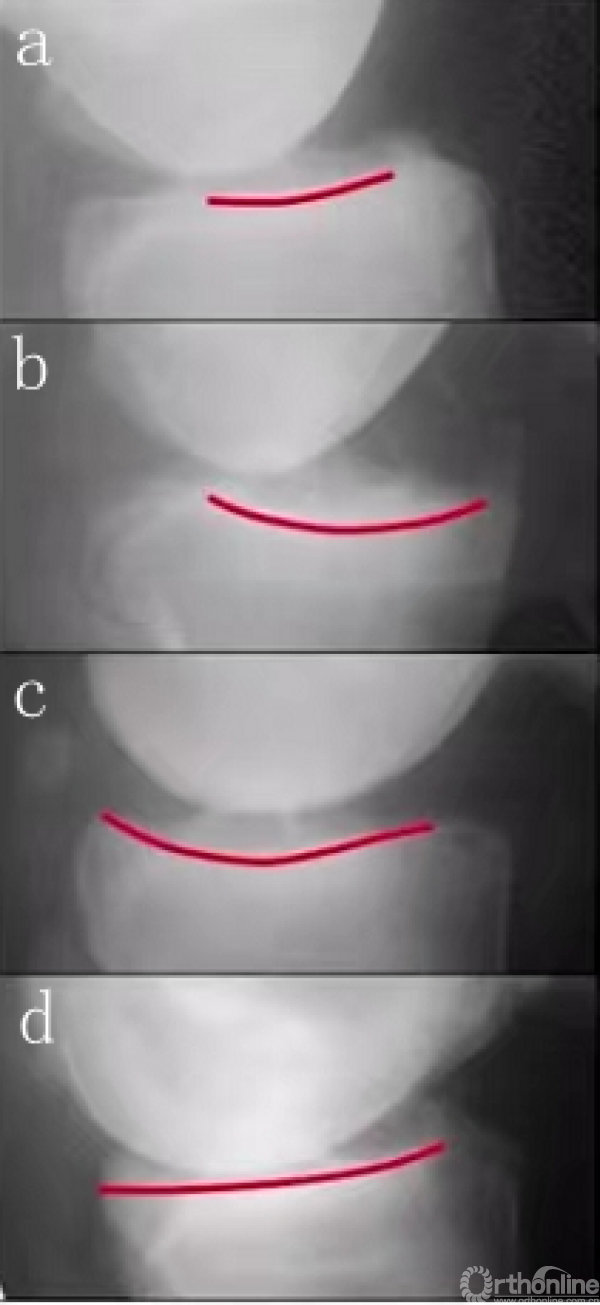

5. ACL 韧带功能完整

双髁重叠侧位片检查。a.ACL功能完好;b.ACL功能完好;c.ACL缺失;d.ACL缺失(半脱位)